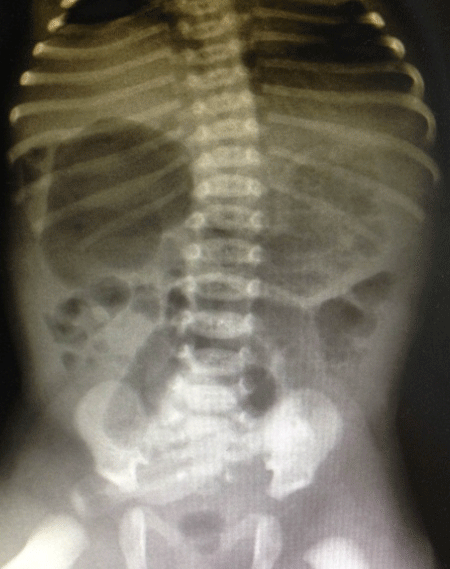

A full-term 2610g male neonate was admitted to the intensive care unit (NICU) with an antenatal history significant for a “double bubble” detected during the second trimester ultra sound examination (Fig. 1). A presumed diagnosis of duodenal stenosis/atresia was made with further karyotyping and anomaly scan showing no abnormalities. The antenatal imaging performed in the third trimester re-confirmed the findings of a double-bubble with no other anomalies being identified. Born at 38 +2/7 weeks, with APGAR scores of 7 and 9, the neonate had mild fullness of the right upper quadrant on clinical exam but no palpable mass. A supine abdominal x-ray revealed a dilated small bowel loop in the right upper quadrant with distal bowel gas, which was interpreted as a possible mega duodenum due to obstruction at that site consistent with the antenatal “double bubble” finding (Fig. 2). Patient then underwent an upper gastrointestinal series (UGI), which initially revealed no evidence of gastric outlet and duodenal obstruction or malrotation. However, subsequent delayed films showed of a space-occupying lesion in the right upper quadrant with a characteristic displacement of small bowel loops. Its subsequent opacification on delayed films was suggestive of a duplication cyst (Fig. 3). No evidence of bowel obstruction was seen. A post-natal ultrasound was not considered necessary in view of the findings on the UGI series.

Figure 2: Neonatal flat plate, large gas bubble in RUQ suggestive of partial duodenal obstruction |